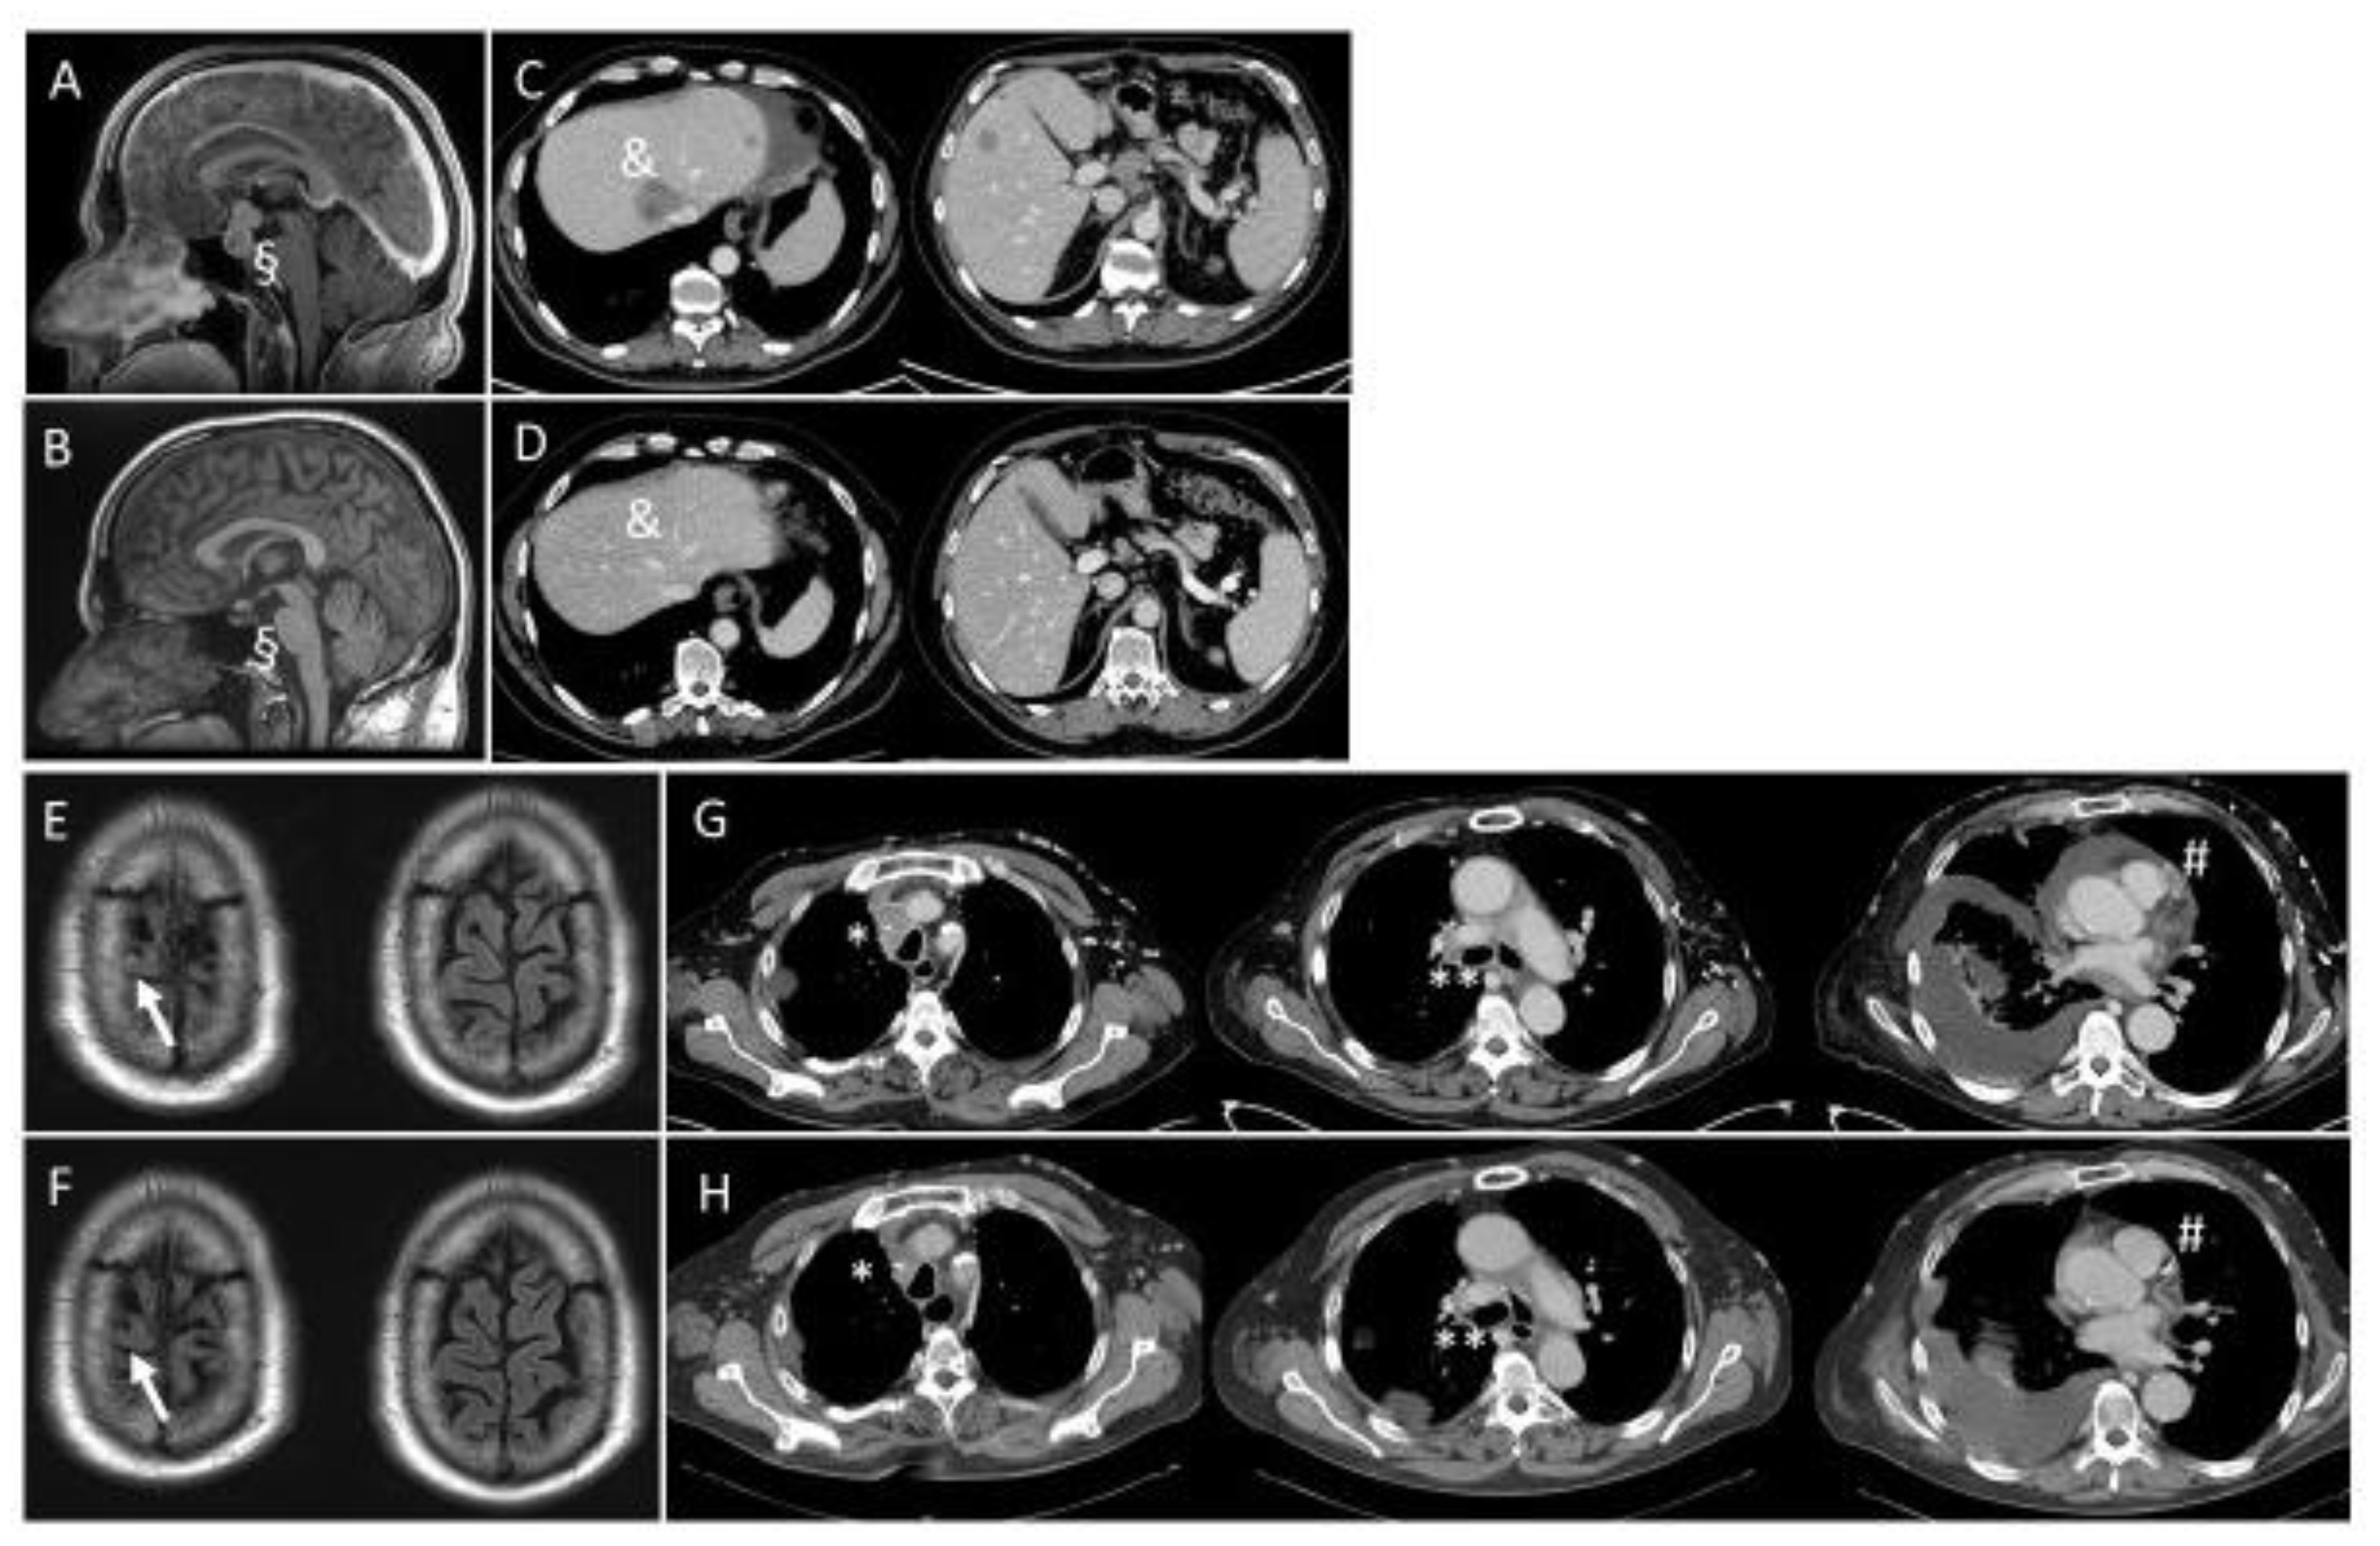

3.2. Characteristics of NTRK-Fusion-Positive Patients